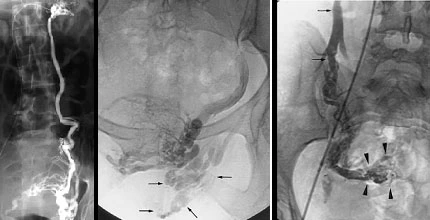

Molte donne convivono con questi sintomi per anni senza ricevere una diagnosi corretta, perché il varicocele femminile può essere difficile da individuare con i normali esami ginecologici. Tuttavia, riconoscerlo è importante perché oggi esistono trattamenti mini-invasivi che possono risolvere il problema in modo efficace e sicuro, restituendo benessere e sollievo duraturo.